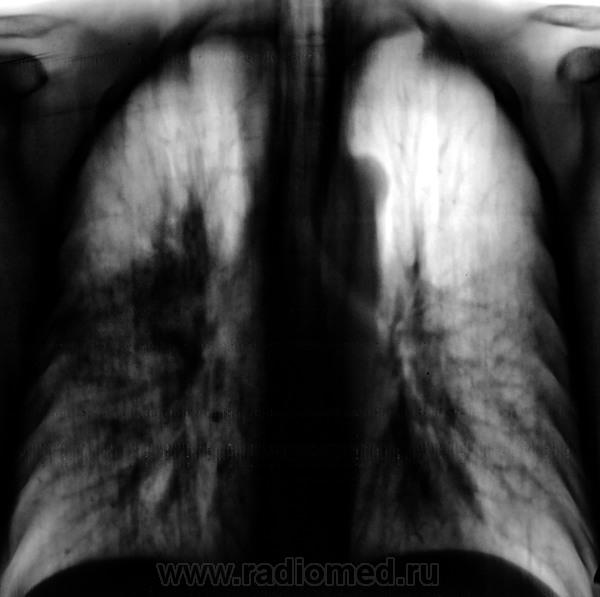

Двусторонняя интерстициальная. Гипертрофия правого корня, перисциссурит малой щели справа. Как бы не вылез центральный справа с лимфогенными метастазами.

В пользу лимфангита еще преимущественное распространение в средних и нижних отделах, неструктурные корни, еще cuffing (разбухание?) стенки бронхов, подчеркнутость междолевых щелей (на боковом хорошо видно, средняя доля "выделена")

Если КТ под рукой есть, то лучше не тянуть время.. Изменения явно интерстициальные, на простую пневмонию никак не тянут. Было несколько пациентов с раковым лимфангитом - выглядело это все именно так как на этой ФЛГ

+1. Пнемония как уже сказано, интерстициальная. В дифференциально-диагностический ряд можно выставить и раковый лимфангаит, оздачить клиницистов, но как-то в этом плане не очень убедительно.

Наличие интерстициальных и узелковых изменений легких, в сочетании с патологией плевры, предполагает наличие лимфангического карциноматоза.